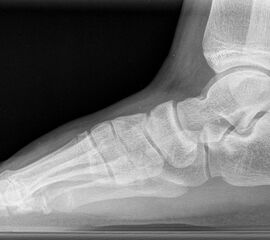

Standard ist die belastete Röntgenaufnahme des Fußes dorso-plantar und seitlich. Günstig ist eine Röhrenkippung von 10°-20°, um die Gelenke der Lisfranc-Linie einsehen zu können.

Ergänzend kann eine Schrägaufnahme hilfreich sein. Bei Metatarsalgien oder Pathologien der Sesambeine liefert die Sprinteraufnahme zusätzliche Informationen. Bei einer Pes planovalgus Fehlstellung wird ergänzend ein Saltzman view durchgeführt.

• Elevation/ Plantarisierung I. Strahl